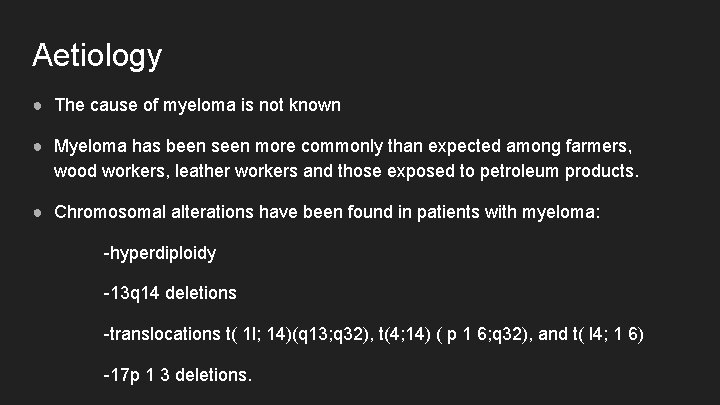

Aetiology ● The cause of myeloma is not known ● Myeloma has been seen more commonly than expected among farmers, wood workers, leather workers and those exposed to petroleum products. ● Chromosomal alterations have been found in patients with myeloma: -hyperdiploidy -13 q 14 deletions -translocations t( 1 l; 14)(q 13; q 32), t(4; 14) ( p 1 6; q 32), and t( l 4; 1 6) -17 p 1 3 deletions.